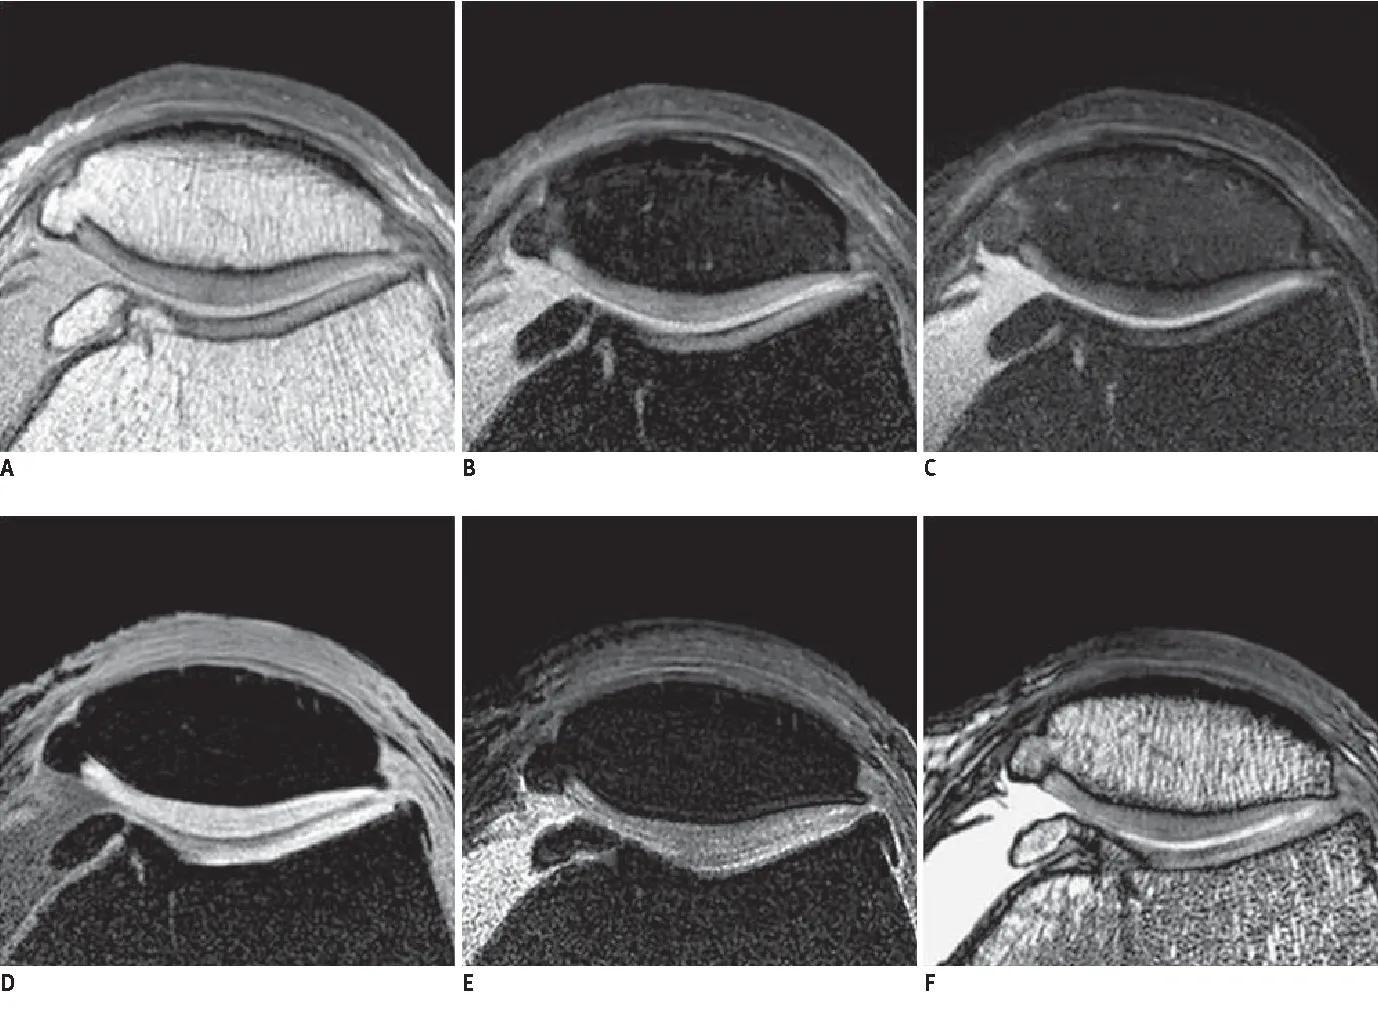

如果您想彻底的了解一下我们自己的膝关节到底有没有以上的问题,那么膝关节的核磁检查是最优选,不仅可以判断髌骨的外倾外移的程度,同时可以发现软骨是否存在损伤关节内,其他的结构是否有问题,这对于医生进行治疗抉择的时候起到的作用是非常大的。